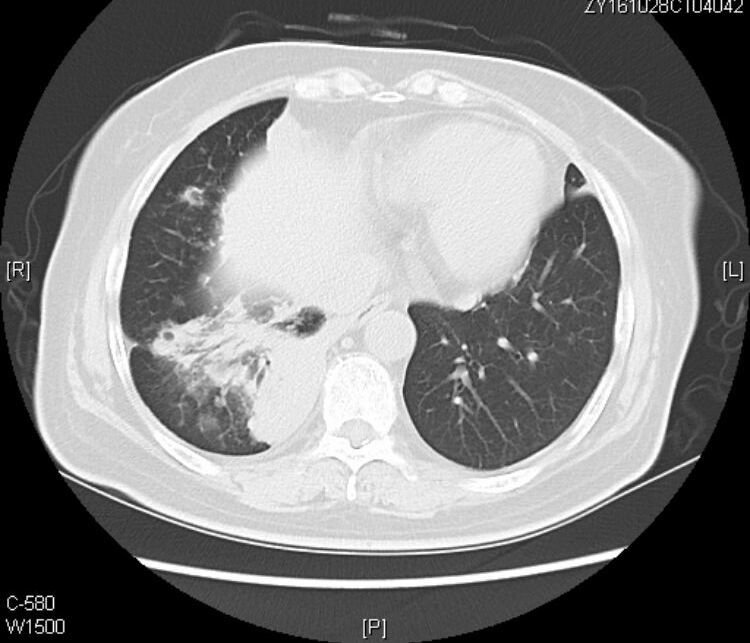

接着看她往下的CT层面:

从CT片上我们可以看到:老人的黏液腺癌还发生了气道转移。

什么是气道转移:

定义:癌细胞从原发灶通过气道非连续性传播到邻近或远端肺实质。

CT提示气道播散的征象包括:多发小叶中心结节,分支模糊呈树芽征,通常边界不清,可见磨玻璃影。

1.气道播散形成的结节呈聚集分布,可以融合增大,有时也可形成空腔。

2.当转移灶远离原发灶时,所形成结节多分布于肺叶下部。

3.在患有肺腺癌的患者CT中发现持续存在或逐渐增长的小叶中心结节时,应考虑到气道转移的可能性,尤其是这些结节伴有侵蚀性、粘液性,呈乳头状或微乳头状分型。